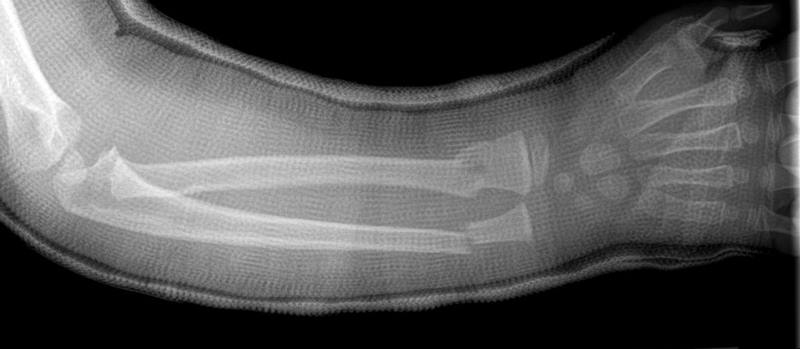

ALWAYS HERE TO HELP KIDS: Injured Children Will Always Remain Priority For Me. Mom Drove 2 Hours For Me To Fix Her Child's Arm . . Though Broken For 3 Weeks Now, The End Result Looks Promising Primum Non Nocere, #DoctorDan

ALWAYS HERE TO HELP KIDS: Injured Children Will Always Remain Priority For Me. Mom Drove 2 Hours For Me To Fix Her Child's Arm . . Though Broken For 3 Weeks Now, The End Result Looks Promising